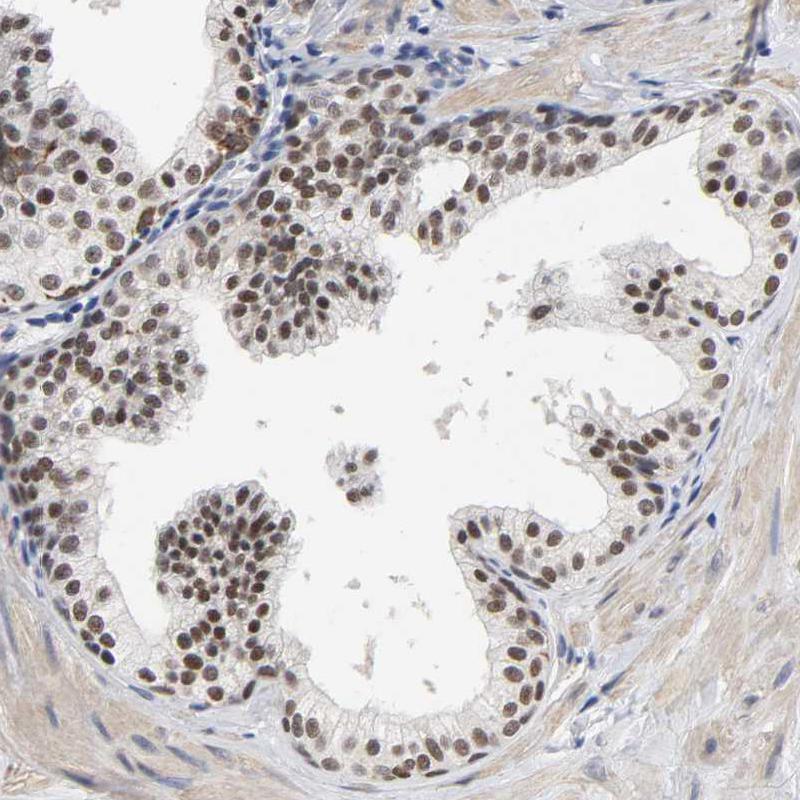

Immunohistochemical staining of human prostate shows strong nuclear positivity in glandular cells.